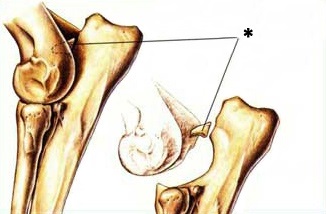

feldolgozza fragmentumok eshet az ízületi üregbe és ásványi. Az ilyen szabad hondromnye test is nevezik „ízületi egerek”, amelyek vándorolnak egyik helyről a másikra közös.

A - ás porcszövet eredetű exostosisok (kinövések) a condylus humerus;

B - exostosisok a kampó alakú nyúlvány;

B - a porc melletti sclerosis a ker. Vágás után blokk;

G - exostosisok a cranialis része a sugár.